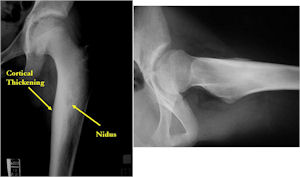

Plain X-Rays:

- Lucent nidus surrounded by a zone of marked sclerosis

- The nidus may demonstrate mineralization/ossification usually from the center outward that appears as a central zone of density within the nidus

- A nidus that is heavily ossified may blend in with the surrounding sclerosis and be difficult to detect on a plain x-ray.

- Periosteal bone is solid, rarely lamellated

- Cortical and subperiosteal osteoid osteomas are usually associated with much more reactive sclerosis than medullary tumors

- The periosteal reaction is continuous and often appears as cortical thickening (benign appearing reaction)

- Intracapsular osteoid osteomas are difficult to identify because there is no periosteum in the intracapsular region and hence a periosteal reaction does not occur.